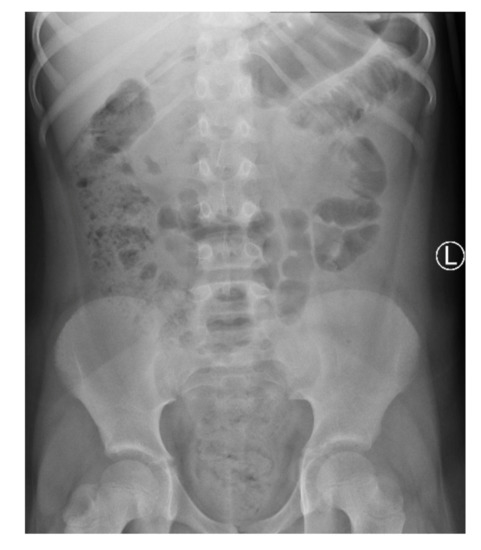

The patient was discharged after 7 days of hospitalization. Oral antibiotic therapy was continued for the next 5 days. Two weeks after the hospitalization, a follow-up visit to the pediatric surgery outpatient clinic took place. The patient did not report any complaints. A follow-up ultrasound examination two weeks after hospitalization showed regression of the abdominal lesions—adipose tissue in the middle-right epigastrium had still partially increased echogenicity, but with neither increased vascularity on Doppler nor fluid collections (Figure 5).

Figure 5. The abdominal ultrasound performed 2 weeks after hospitalization: further regression of abdominal lesions.